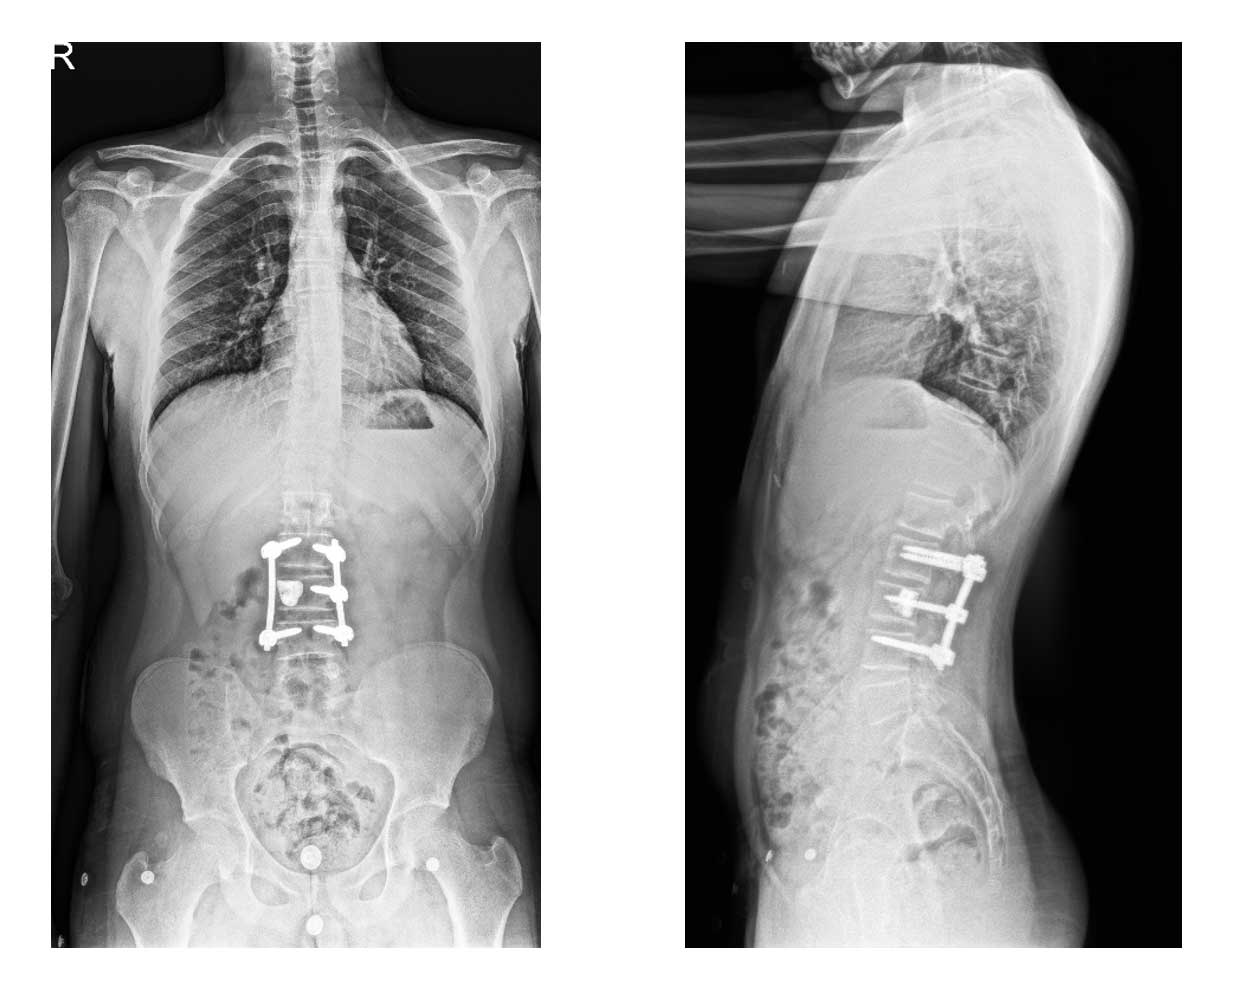

Ameliyat Sonrası: Röntgende tümör temizlendikten sonra oluşan boşluğa kemik çimentosu uygulanımı ve posterior enstrümentasyon işlemi görülmekte